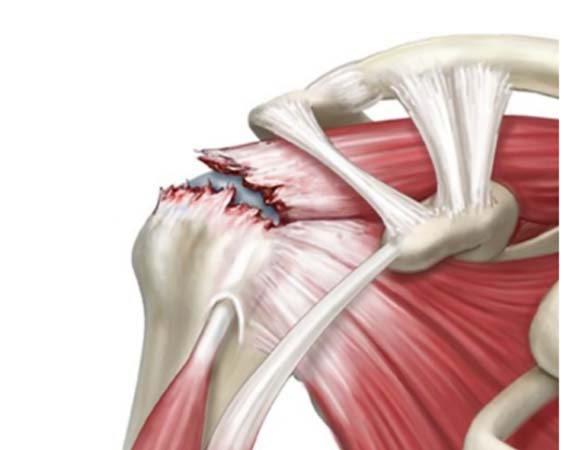

LESÃO DO MANGUITO ROTADOR

O manguito rotador é composto por 4 músculos: supraespinhal, infraespinhal, subescapular e redondo menor. A principal função desse grupo muscular e realizar os movimentos do ombro, bem como a estabilização da articulação. As lesões do manguito rotador constituem a ruptura total ou parcial desses tendões.. As causas da lesão podem ser degenerativas e traumáticas. No paciente idoso, com o processo de degeneração o tendão perde as suas propriedades fibroelásticas e torna-se susceptível ao surgimento dessas lesões. As causas traumáticas são observadas habitualmente em pacientes jovens, mas pode acometer os pacientes mais velhos também. Sintomas como dor no ombro e dificuldade para realizar a elevação do ombro e movimentos rotacionais são as queixas mais frequentes. O tratamento e individualizado para cada paciente. Mas as lesões com ruptura total ou lesões parciais com mais de 50% de extensão, associado a quadro de dor e dificuldade para realizar os movimentos do ombro, tendem a necessitar de cirurgia. Para lesões parciais com menos de 50% com quadro de dor pequeno e um bom movimento do ombro habitualmente indica-se a reabilitação com fisioterapia. A cirurgia utilizado é a artroscopia do ombro, podendo-se realizar a cirurgia aberta em raros casos. Após o procedimento utiliza-se uma tipoia durante cerca de 35 dias, onde após esse período o paciente iniciará a reabilitação fisioterápica.